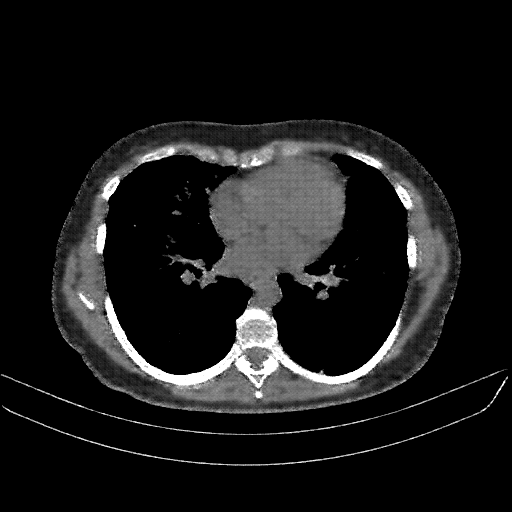

Targeted Slice 70 - Mediastinum Window Analysis (Generated vs Real Venous)

0.762

Mediastinum SSIM

47.9

Mediastinum RMSE

17.1

Mediastinum MAE

Average Mediastinum Window Metrics Across All Slices (133 slices) - Generated vs Real Venous

0.740

Mediastinum SSIM (Avg)

46.9

Mediastinum RMSE (Avg)

17.0

Mediastinum MAE (Avg)

Generated VENOUS CT scan (A→B translation)

No window - Raw intensity values

Mediastinum window (WL 40, WW 400 β†’ Low βˆ’160, High +240)